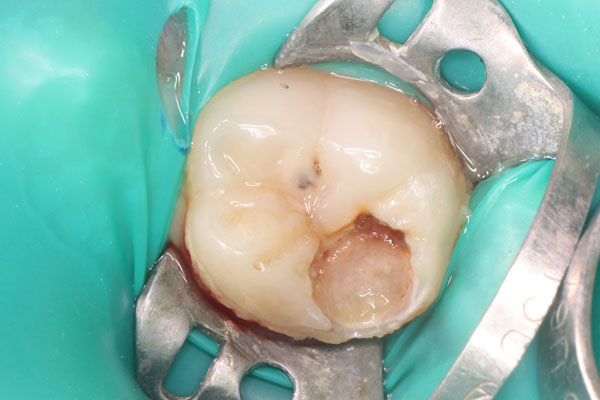

Лечение пульпита: фото До и После

- Если необходима чистка каналов, то десна предварительно обезболивается, а сам зуб изолируется, чтобы во время лечения туда не попадала слюна.

- Зуб рассверливается до пульпы, пораженные ткани (иногда вся пульпа целиком) удаляются, а каналы обеззараживаются.